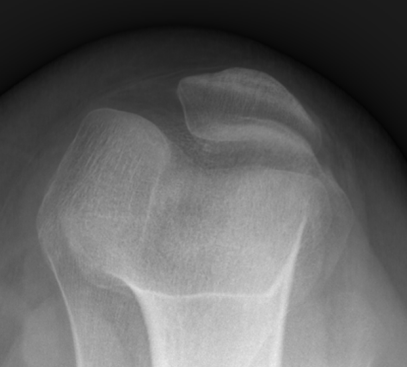

随着现在体育运动的增加,儿童意外伤害也越来越多,其中“膝盖骨”脱位也逐年增加。“膝盖骨”脱位在医学上称之为髌骨脱位,其定义为髌骨因外伤因素或自身韧带松弛等因素导致其偏离原来的解剖位置,从而产生一系列膝关节疼痛、肿胀、活动受限等症状的疾病。(如下图所示)

1、X 线片

对诊断有很大价值,可以显示髌骨形态和位置是否正常,常规应拍膝关节正侧位及髌骨轴位 X 线片,髌骨轴位X线片对髌骨向外侧偏斜及半脱位有肯定的意义,可显示髌骨及滑车发育不良,髌股关节面不相适应及髌骨移位情况,可通过测量髌骨脱位相关角度,以明确诊断。

正常髌骨

脱位髌骨